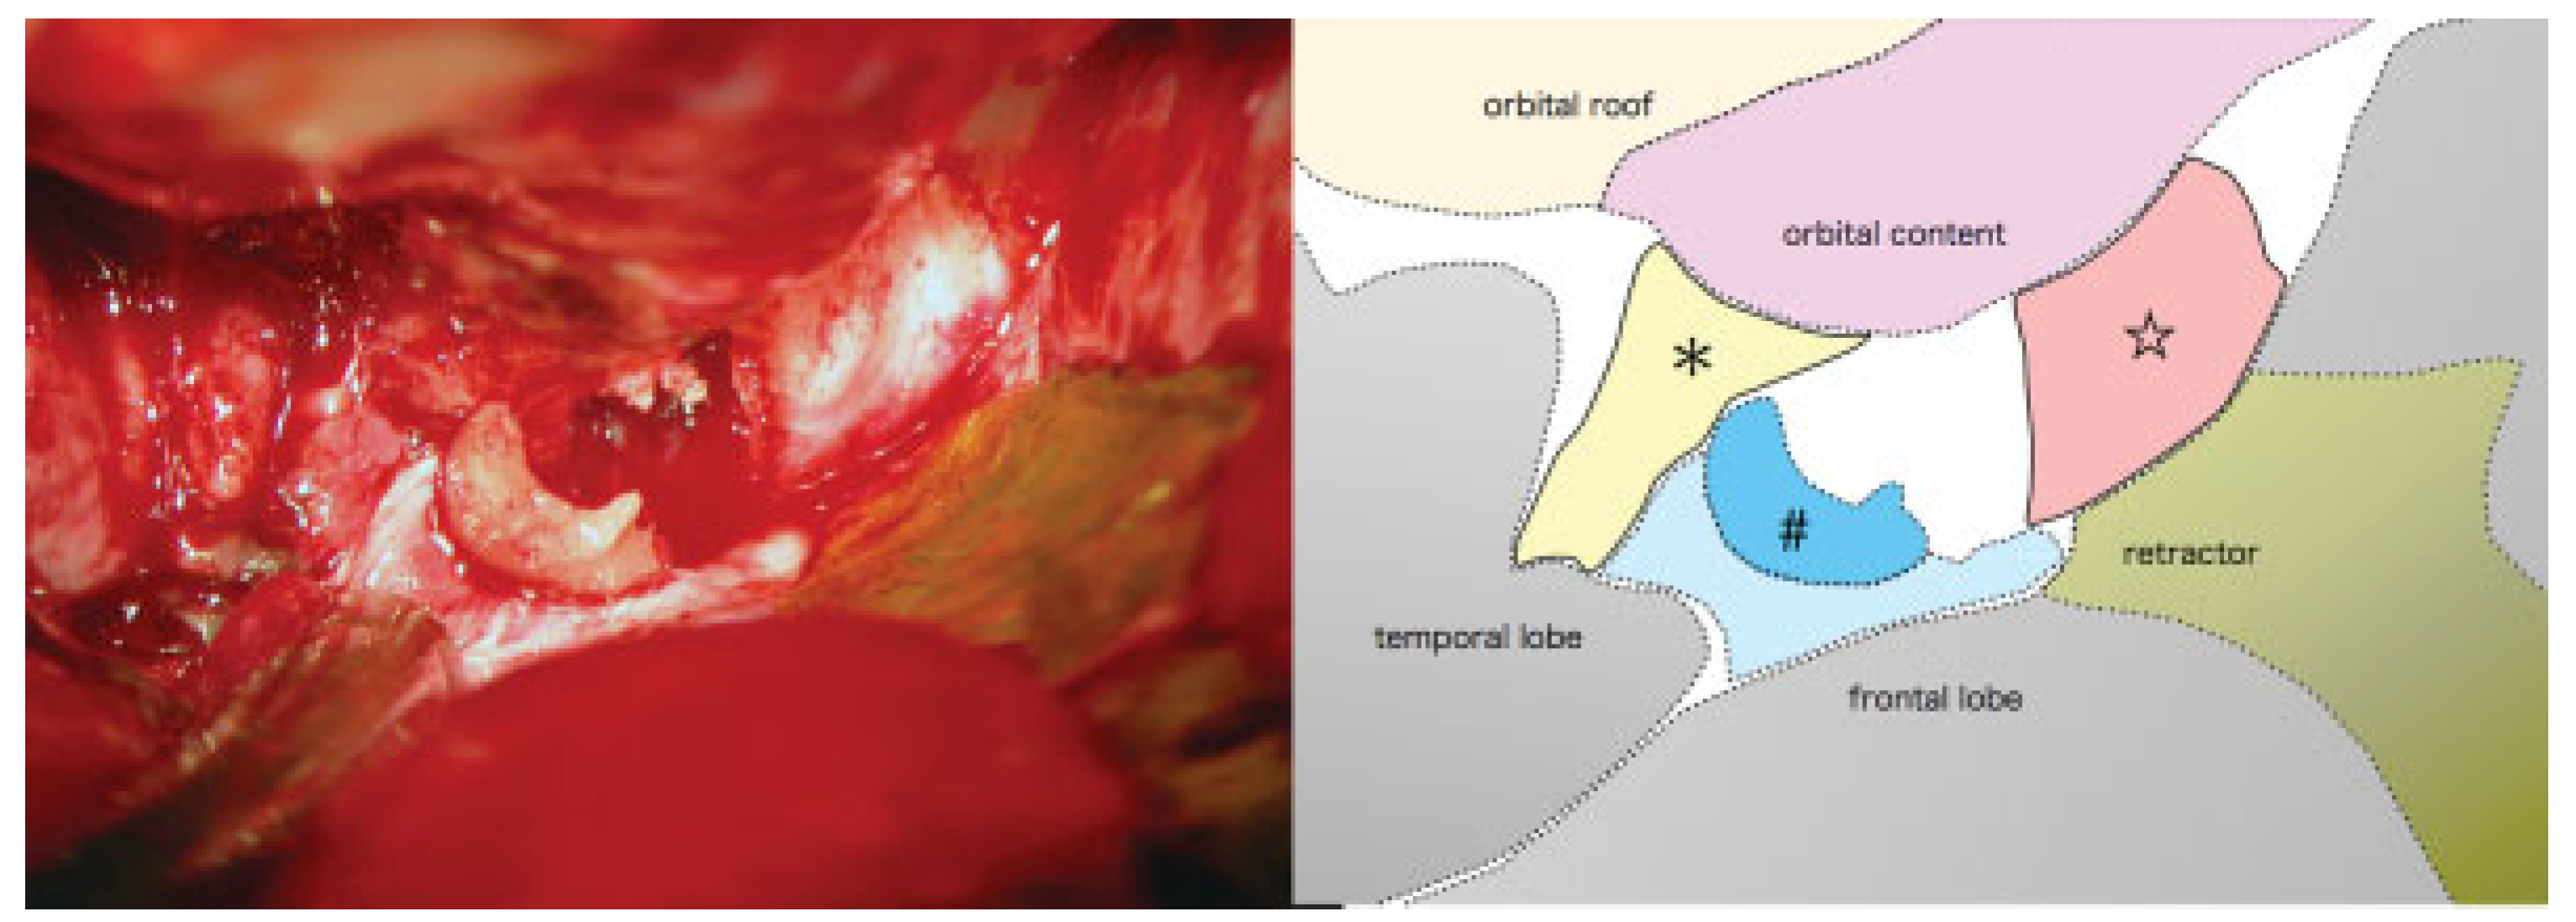

Surgery began six hours after his accident. First, using a coronal incision, the medially displaced left zygoma and inferiorly displaced superior orbital rim fractures were reduced to decrease the elevated orbital pressure and to relieve the compression of the superior orbital fissure. A frontotemporal craniotomy was made. The lesser wing of the sphenoid and the base of the left anterior clinoid process were widely resected sequentially by the epidural approach (Figure 4). Sufficient decompression of the superior orbital fissure and the optic canal was accomplished successively (Figure 5 and Figure 6). Finally all the fractures were reduced and fixed with titanium plates. The left orbital floor was reconstructed with the calvarial bone graft. After surgery, the patient had a dexamethasone taper over six days to reduce cerebral edema, beginning with a dose of 4 mg/day, on the advice of our neurosurgical consultant.

Figure 4.

After decompression of the superior orbital fissure and the optic canal by the epidural approach using a fronto-temporal craniotomy.

Figure 5.

Close-up view of boxed area in Figure 4. Decompressed bare optic nerve (red ☆); remnant of the left anterior clinoid process (blue #); decompressed superior orbital fissure (yellow *).